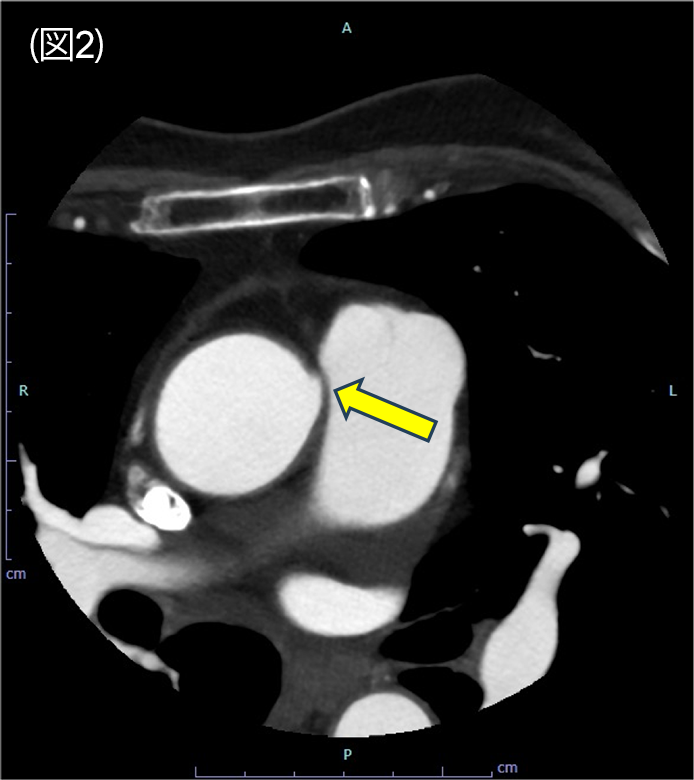

図2.冠動脈CT axial 像

右冠動脈は大動脈と肺動脈の間を走行している。